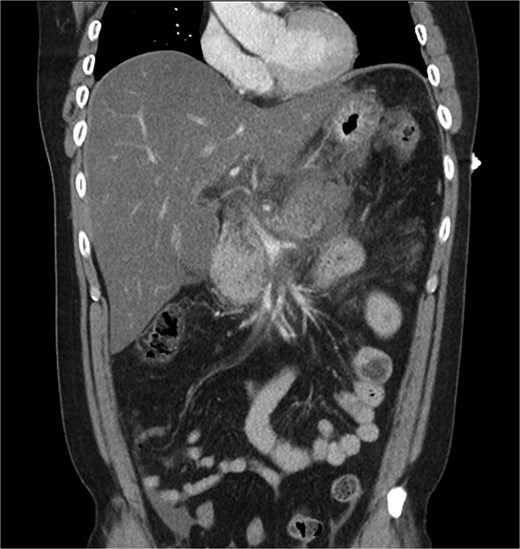

A 39-year-old male presented with one week of worsening epigastric pain radiating to the back, with vomiting, jaundice, and dark urine. His past medical history included depression and alcohol-related liver disease without cirrhosis. On admission he was afebrile, had a soft abdomen with epigastric tenderness worse on palpation, tachycardic, and normotensive. Initial investigations showed a lipase of 2600 U/L, C-reactive protein 238 mg/L, lactate 3.4 mmol/L, and bilirubin 100 μmol/L (Table 1). Abdomen and pelvic computer tomography (CT) demonstrated body and tail pancreatitis, fat stranding, portal vein thrombus, and early necrosis signs, with no choledocholithiasis (Figs 1–3).

Coronal CT image demonstrating body and tail pancreatitis with potential early signs of necrosis.